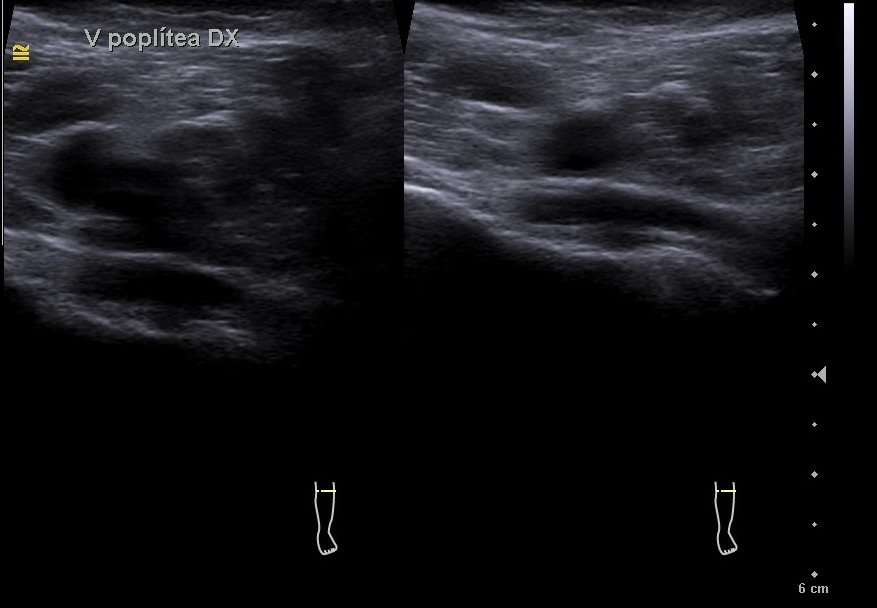

Hallazgos ecográficos

El estudio pone de manifiesto una ocupación trombótica aguda de la vena poplítea de pierna izquierda.

En el estudio se comparó la vena poplítea derecha, la cual a la presión ejercida con la sonda del ecógrafo sí comprimía, lo cual no sucedía con la vena poplítea izquierda.

Ambas venas femorales bilaterales eran permeables.